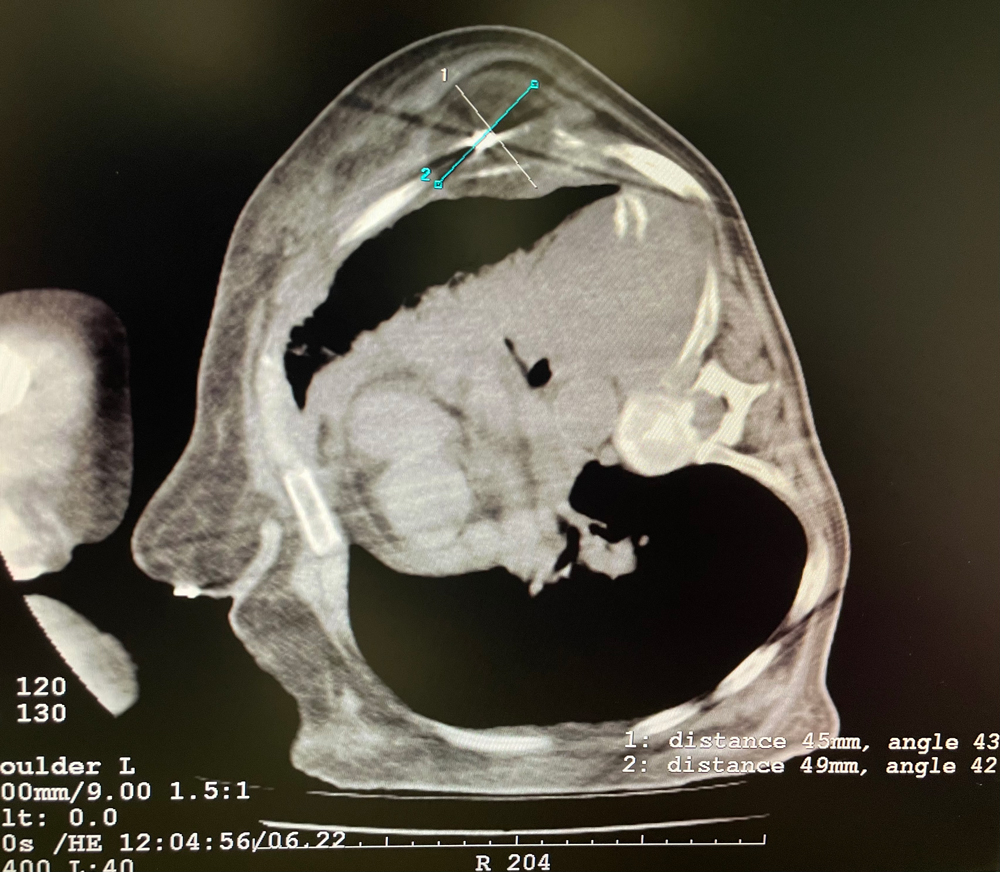

患者二

女,42岁,复发性脂肪瘤,病灶位于右侧膝关节,直径大小13cm。采用双针方案,共进行6个冻融循环,最大冰球直径达8.2cm,术中多方位治疗全面覆盖病灶范围。患者术后状况良好。